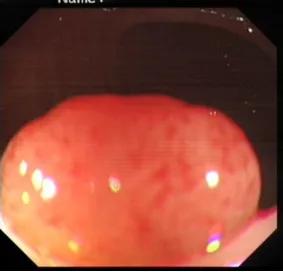

十年前,陳先生(化名)因常規(guī)體檢到羅湖區(qū)人民醫(yī)院消化內(nèi)科做結(jié)腸鏡檢查。檢查順利,但醫(yī)生在他的結(jié)腸里發(fā)現(xiàn)多個(gè)大小不一的息肉,有的像“小蘑菇”,有的是平坦隆起,其中直腸部位的息肉被確診為有明確癌變風(fēng)險(xiǎn)的絨毛狀腺瘤性息肉。

10年前腸鏡下看到的乙狀結(jié)腸息肉,表面尚光滑,但已具風(fēng)險(xiǎn)。